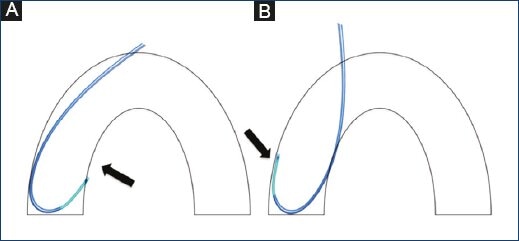

We included 327 consecutive patients undergoing coronary assessment and treatment for whom a single catheter was used for the entire procedure. Patients were enrolled between January 2014 and December 2015. An Ikari left catheter was used (Terumo Medical Corporation, Tokyo, Japan). For patients shorter than 5'6", the Ikari 3.5 cm curve left catheter was used. For patients over 5'6", the 4 cm curve catheter was used (Fig. 1).

An additional backup catheter (Voda, XB, and EBU) may improve procedural success with different modalities. However, there have been limitations with treating left main lesions, short left main with ostial circumflex lesions and right coronary lesions (Fig. 3). The Amplatz right catheter facilitates ostial access to right proximal, mid-, or distal coronary lesions. However, when significant tortuosity is present, it may be difficult to stabilize or advance the catheter. Furthermore, it does not offer adequate support, stability or control when treating the left coronary system. The Amplatz left catheter may provide good support and stability to the RCA and may ease balloon and stent placement. Nevertheless, when treating proximal and ostial lesions, the complexity might increase. In addition, it does not offer good support for interventions of the LCA through the transfemoral approach (Figs 4A-4D).

Figure 4 Diagram of the Amplatz left catheter in the right coronary ostium (A), Amplatz left catheter in the left coronary ostium. Note the low one-point support on the contralateral wall. (B) Right Amplatz catheter in the on the right coronary ostium. Note the absence of support on the contralateral wall. (C) Right Amplatz catheter in the left coronary ostium. Note the lack of support on the contralateral wall when performed by the transradial approach (D).